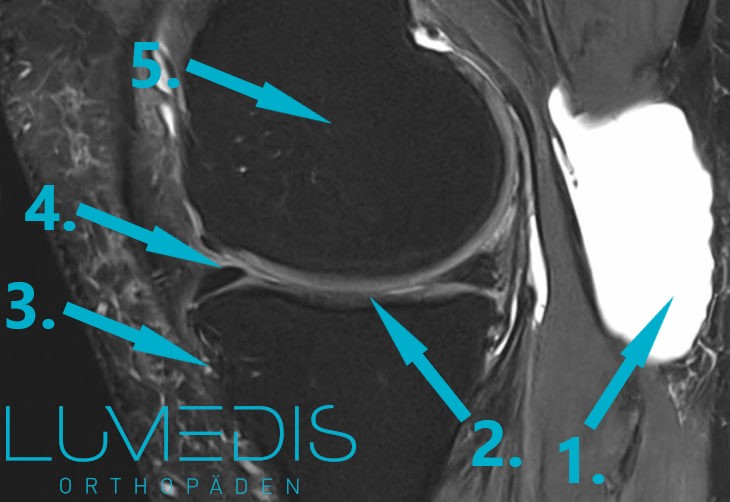

MRT einers Kniegelenks seitlich (T2)

MRT Knie: Bakerzyste in der Kniekehle

MRT eines seitlichen Kniegelenks mit einer einer Bakerzyste (T2)

Die MRT (Magnetresonanztomographie) ist das am höchsten auflösende Bildgebungsverfahren.

Hiermit lässt sich die genaue Lokalisation und Ausdehnung der Bakerzyste und ihre Verbindung zur Gelenkkapsel darstellen.

Allerdings ist die MRT kein standardmäßiges Untersuchungsverfahren zum Nachweis einer Bakerzyste.

Nur wenn aus den gewonnen Informationen eine Mehrwert für die Therapie entsteht, ist ein MRT vom Kniegelenk sinnvoll.

MRT eines rechten Kniegelenks seitlich (T2) mit Bakerzyste